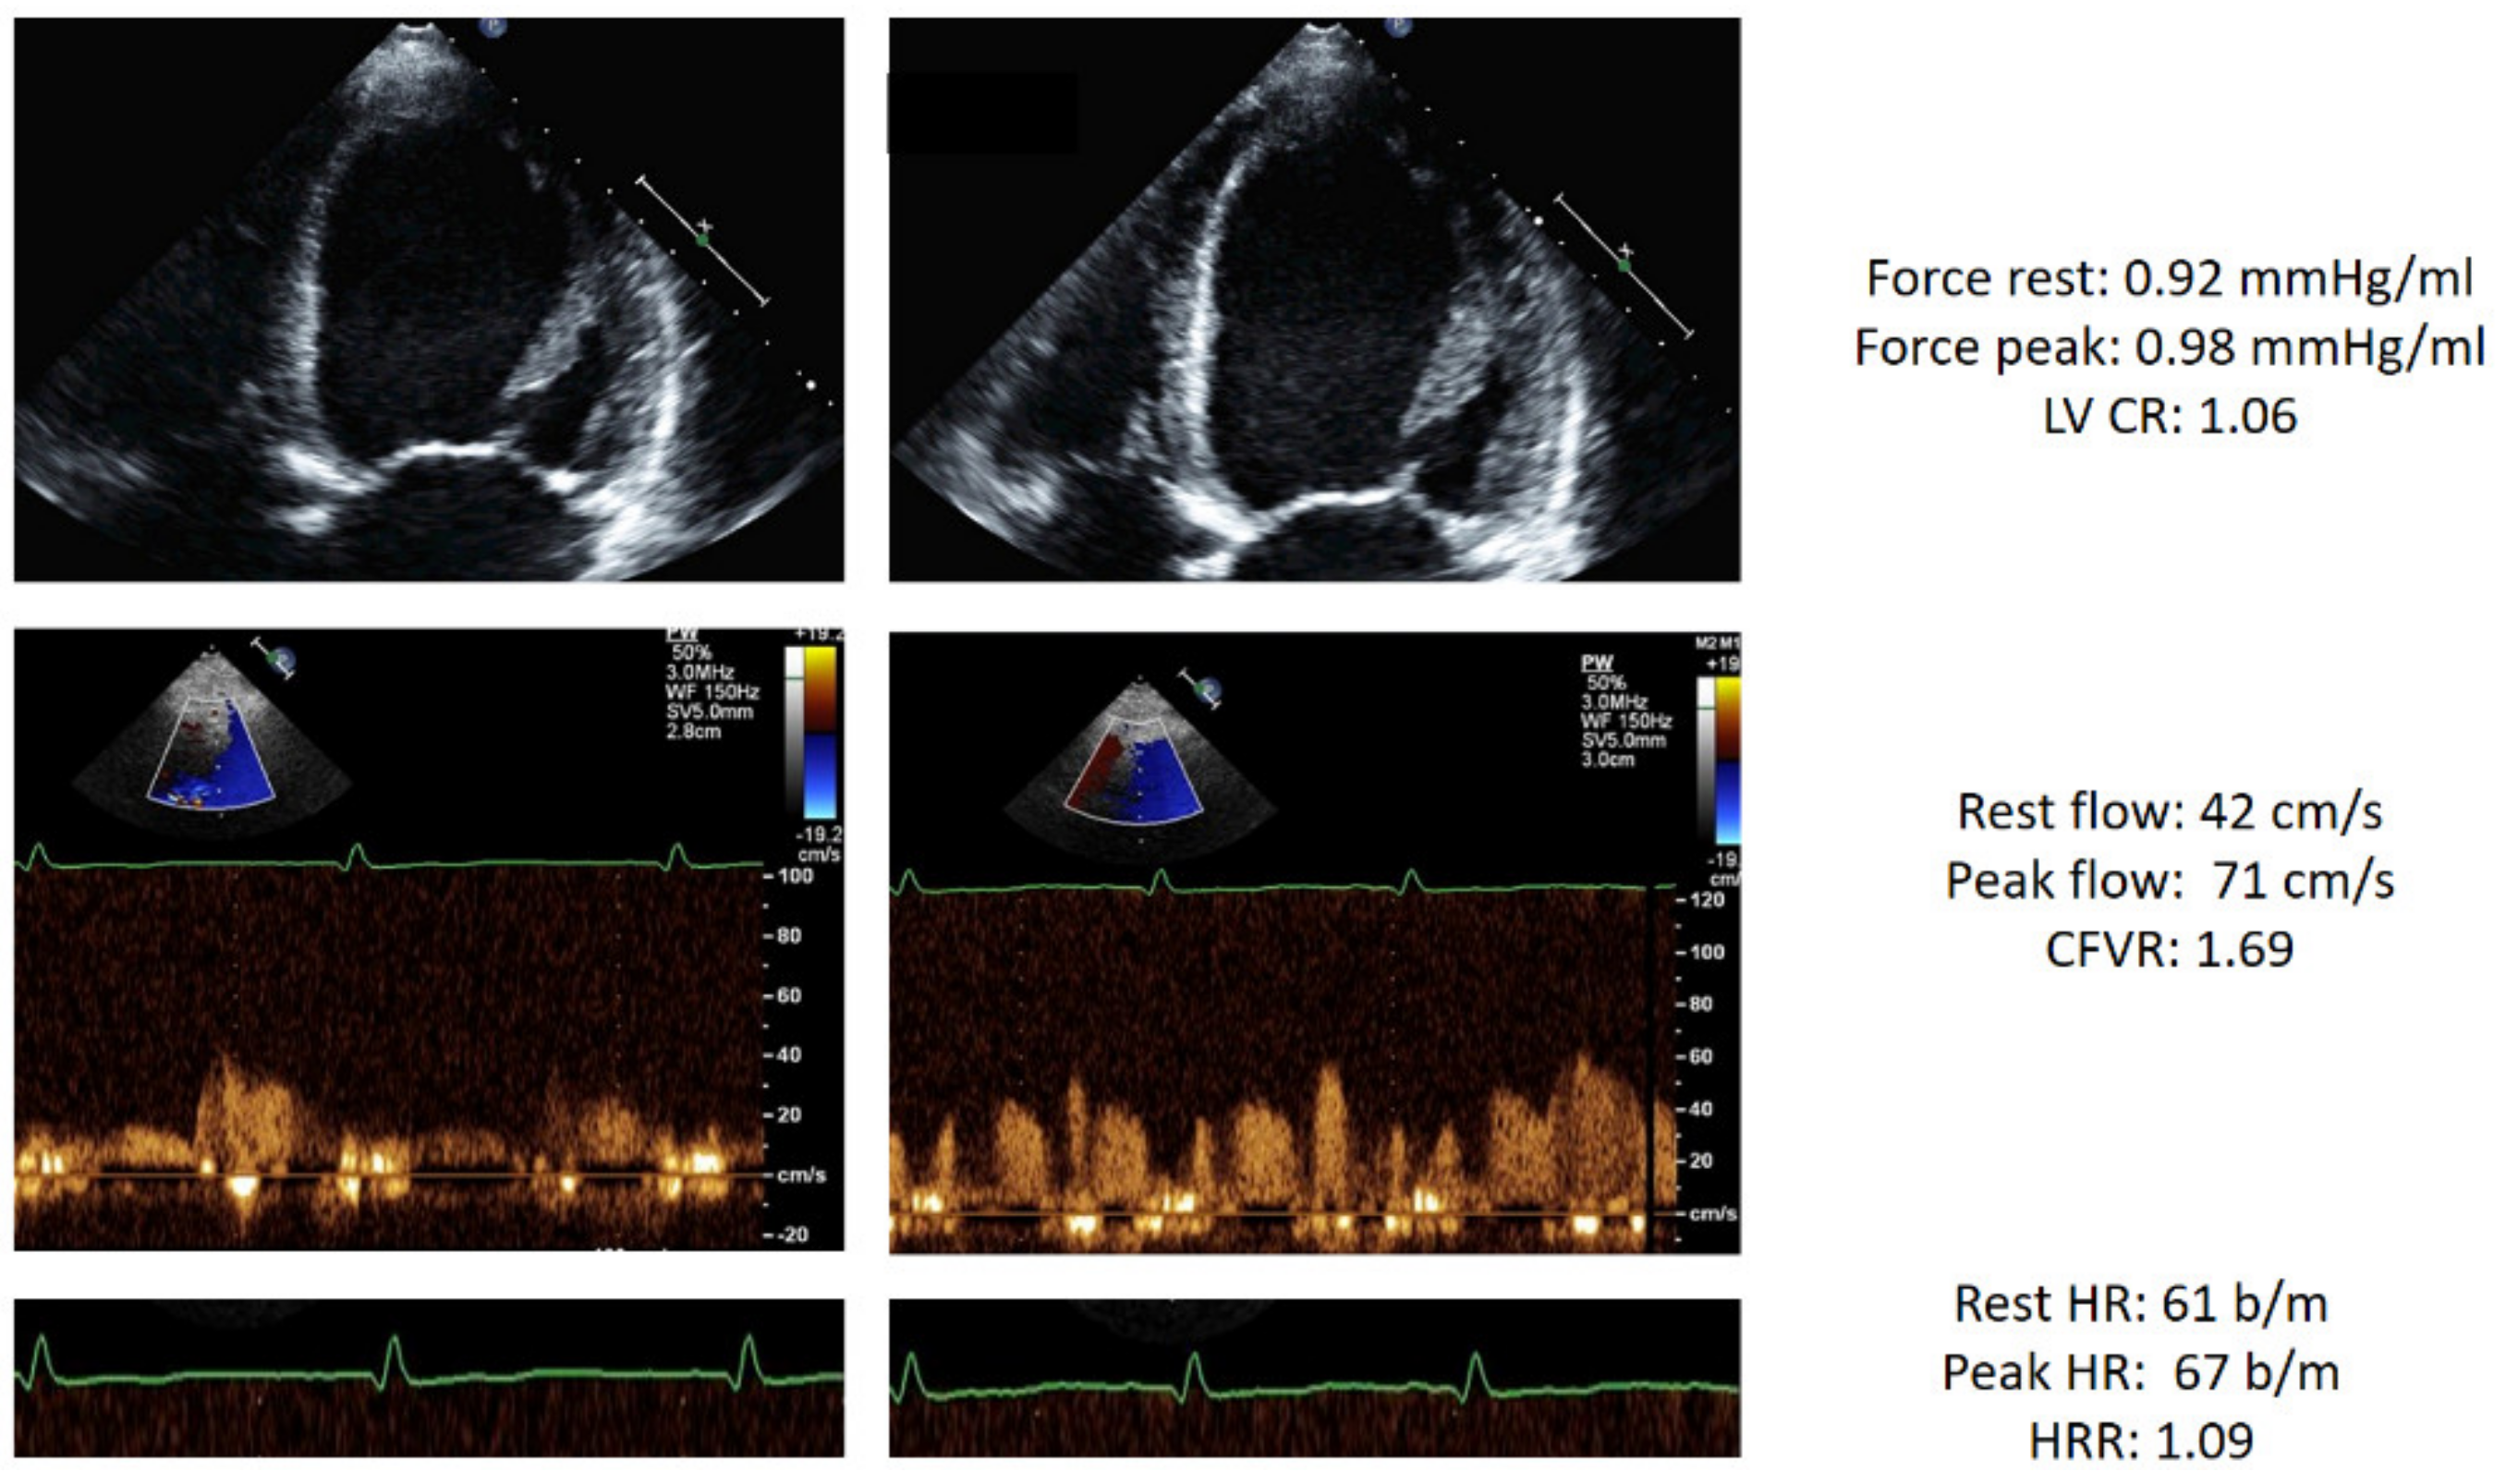

| Rest force (mmHg/mL) | 3.0 ± 2.0 | 4.7 ± 1.7 | 4.4 ± 1.1 | 1.1 ± 0.5 | <0.001 |

| Stress force (mmHg/mL) | 4.0 ± 3.3 | 6.6 ± 3.1 | 3.0 ± 1.8 | 1.2 ± 1.1 | <0.001 |

| LV CR | 1.24 ± 0.38 | 1.41 ± 0.39 | 1.20 ± 0.25 | 1.02 ± 0.33 | <0.001 |

| Rest CFV (cm/s) | 29.6 ± 8.4 | 27.6 ± 8.5 | 31.0 ± 7.7 | 31.4 ± 8.3 | <0.001 |

| Stress CFV(cm/s) | 65.5 ± 22.6 | 64.3 ± 16.9 | 68.2 ± 15.9 | 65.1 ± 22.6 | 0.108 |

| CFVR | 2.24 ± 0.47 | 2.38 ± 0.39 | 2.24 ± 0.42 | 2.06 ± 0.54 | <0.001 |

| Rest HR (bpm) | 70.7 ± 11.3 | 69.5 ± 10.6 | 69.3 ± 10.8 | 73.3 ± 12.2 | <0.001 |

| Peak HR (bpm) | 88.6 ± 15.0 | 90.4 ± 16.1 | 86.9 ± 13.6 | 87.5 ± 14.1 | 0.030 |

| HRR | 1.26 ± 0.17 | 1.31 ± 0.18 | 1.26 ± 0.16 | 1.20 ± 0.16 | <0.001 |